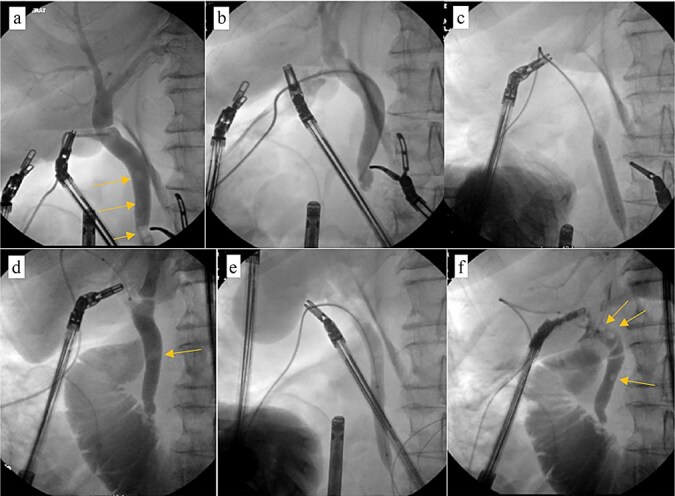

Patient was brought to the OR, induced, and the peritoneum was accessed via optical view trocar. After the critical view of safety was obtained, the cystic duct was partially transected and a 6-French ureteral catheter was threaded through the duct and into the CBD. Initial cholangiogram showed complete obstruction of the distal CBD. A 0.035 guidewire was advanced through the ureteral catheter. The ureteral catheter was then exchanged for a 9 × 40 mm long vascular balloon catheter. The balloon was then centered at the ampulla of vater and inflated to its nominal pressure for 5 min. A small indentation was noticed at the level of the ampulla once the balloon was fully insufflated, as expected. The completion cholangiogram showed prompt evacuation of contrast into the duodenum. However, numerous “floating” filling defects continued to be present (Fig. 4). The decision was thus made to leave a T-tube in place via a 1-cm longitudinal choledochotomy. The incision was reapproximated around the t-tube with interrupted 4–0 PDS. The vascular balloon catheter was removed, the cystic duct was completely transected, and the gallbladder was dissected off the liver bed.

Patient was discharged home on POD 7 following IV antibiotic completion (Fig. 5). Patient was seen in the ER 1 week later for drainage around the T-tube. Tube study confirmed resolution of CBD obstruction and the patient was discharged from the ER (Fig. 6).